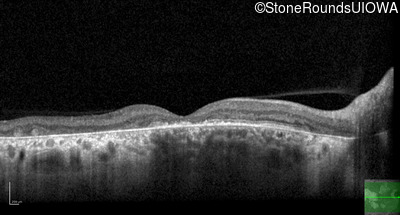

AR Stargardt Disease (IIA)

Age at visit: 56 years

This 56 year old man underwent surgery for strabismus in early childhood. He felt that his vision was good for most of his life, but about 5 years ago he first experienced difficulty following a golf ball in flight.

Diagnosis & molecular findings

Disease Gene Allele 1 variant(s) Allele 2 variant(s) Inheritance mode

AR Stargardt Disease ABCA4 Asn965Ser AAT>AGT Glu2131Lys GAA>AAA AR